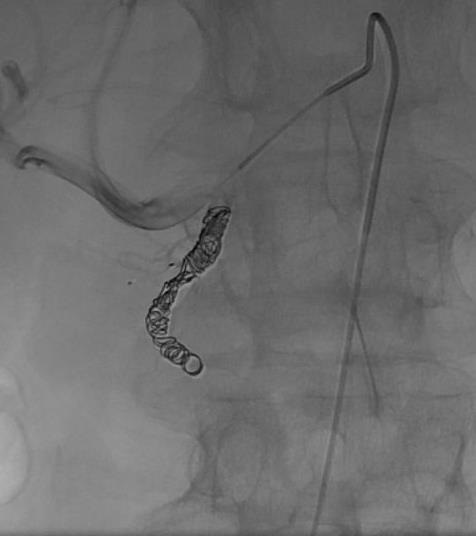

目前已经通过CE Mark,尚没有在美国应用。 MVP-3的临床前研究: 狗的2mm直径的锁骨下动脉,通过0.021“ 微导管进行超选择栓塞

临床研究:放射性栓塞前胰腺动脉栓塞

临床研究:放射性栓塞前,胃右动脉栓塞